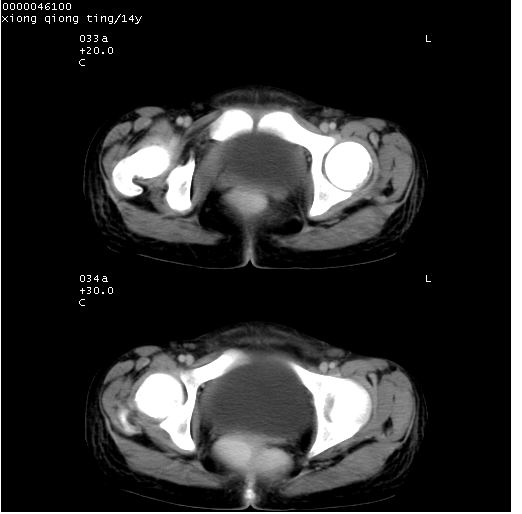

患儿 女,14岁。不规则发热一周,偶感头痛,无抽搐及呕吐。pe:神清,精神差,双侧瞳孔等大等圆,对光反射敏感,双肺未闻及明显啰音,心音有力,腹部触之似揉面感,下腹压痛,无反跳痛。

腹部b超提示:子宫缩小,盆腔积液,肝实质回声密集。

中下腹及盆腔ct轴位平扫+增强扫描(层厚10mm,螺距1.0,重建间隔10mm),图像如下:

(注:患儿检查当日上午9时口服胃肠道对比剂,下午3时许行ct扫描检查,未行对比剂直肠保留灌肠,检查当日患儿腹泻)

中下腹及盆腔ct轴位扫描(ps+ce)提示:腹部肠管明显充气扩张,并见数个不同宽度之气液平面;疑不全性肠梗阻或肠郁张。临床会诊考虑为患儿腹泻,肠郁张所致;后来未经特殊处理,患儿大便恢复正常,亦无腹胀。

临床出院诊断:1)结核性腹膜炎。2)腹膜后淋巴结结核。3)脂肪肝。